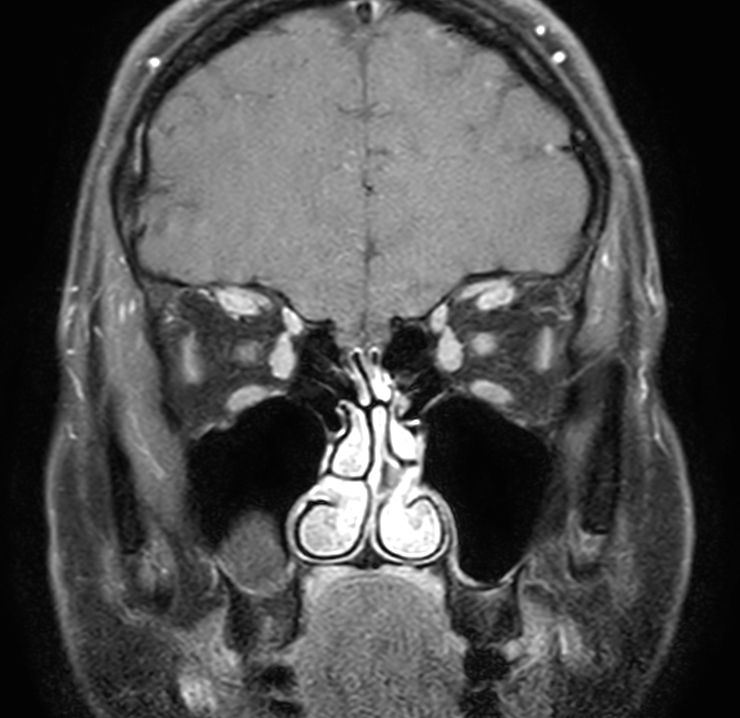

3D VIEW - T1w TSE (coronal reformat)

Pre-Gado

Post-Gado

Coronal T1w TSE mDIXON (In Phase)

Coronal T1w TSE mDIXON (Water only)